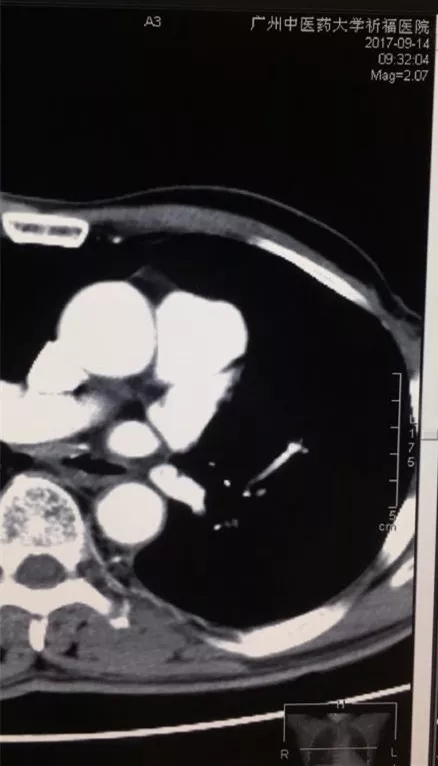

射频深部热疗的原理是利用射频电磁场作用于深部组织,利用热效应选择性破坏、杀伤病变细胞达到治疗目的,其特点是纳米范围的能量释放,其释放的能量利用效率可提升3-4倍。区俊文团队发现,大剂量VitC与mEHT同时结合使用,能令体内VitC峰值浓度显著增加[2],高浓度VitC以其氧化形式脱氢抗坏血酸(DHA)进入细胞后消耗大量还原型谷胱甘肽(GSH)和还原型烟酰胺腺嘌呤二核苷酸磷酸(NADPH),令癌细胞内活性氧簇(ROS)增加,进而引发DNA 损伤和断裂,泛素化蛋白酶体的活化,*终导致癌细胞凋亡。该研究发现这两个配角的组合,能够显著改善晚期NSCLC生活质量,延长生存期,还有部分病例肿瘤病灶显著缩小(图4),生存时间超过5年[1]。而且,从分组来看,上述治疗方法对于腺癌和鳞癌的患者,EGFR(+)与EGFR(-)的患者相比,没有统计学差异,提示,上述治疗方法对于不同病理类型的晚期肺癌患者疗效是相当的。这无疑对于晚期患者来说,多了一个治疗方案的选择,是一个福音。

图4 左图:治疗前:肺门的肿大淋巴结(红色圈内)右图:治疗后,肿大的淋巴结消失